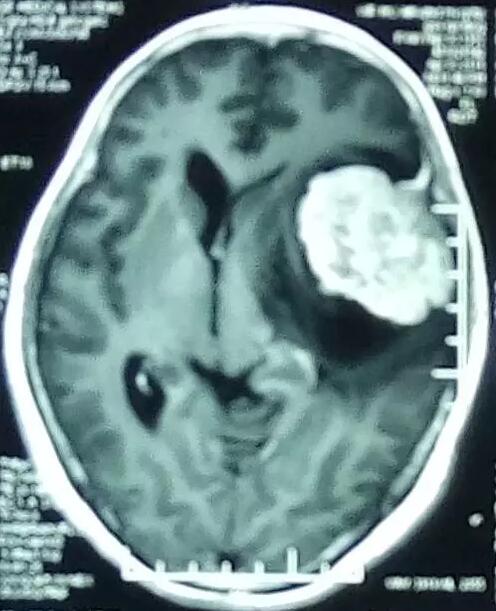

术后复查,显示肿瘤组织全部切除